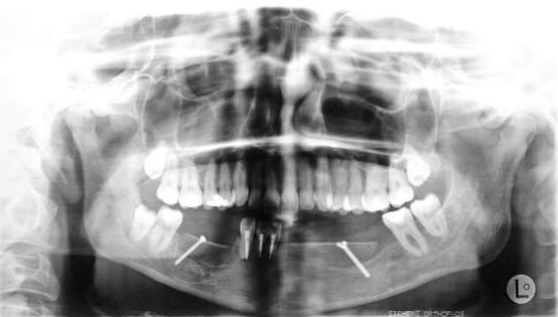

Fig 7: Oktober 2005: trial excision, suspected recurrence fibrosarcoma right lower jaw

Figure 7